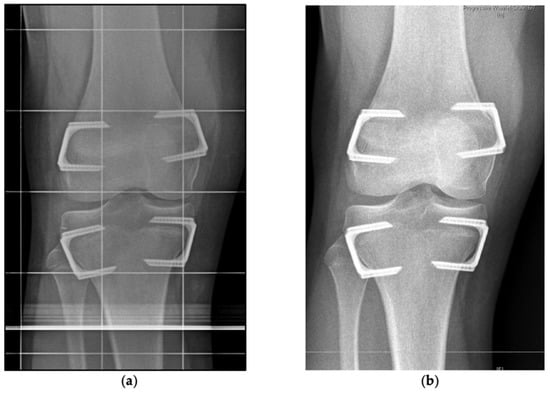

2.2. Indication, Operative Technique, and Applied Implants

2.3. Implants Applied for Epiphysiodesis